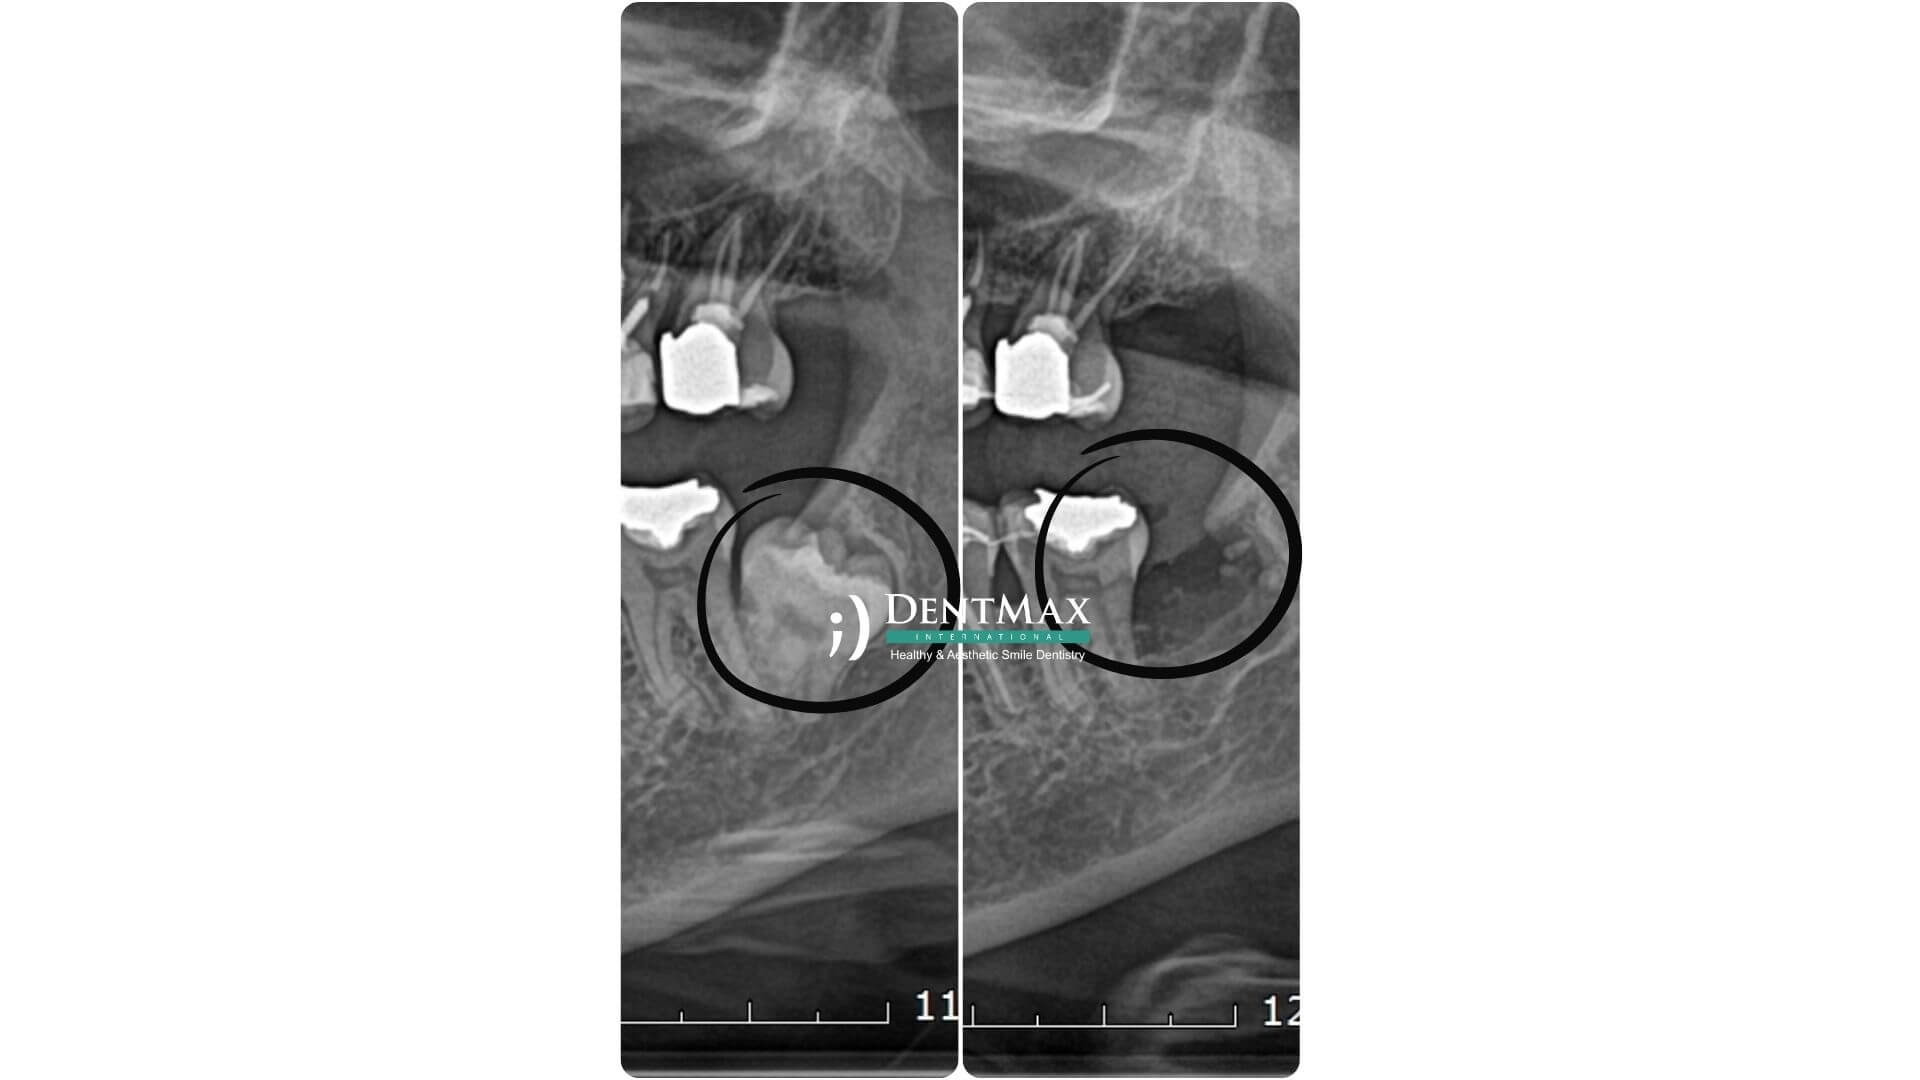

Tomografi ve Tecrübeli Hekim Neden Önemli?

20 yaş dişleri sinir kanallarına veya sinüs boşluklarına çok yakın olabilir.

Tomografi yapılmazsa sinir zedelenmesi, dudakta hissizlik, sinüs zedelenmesi, komşu dişlerde kırık gibi komplikasyon riski artar.

Tecrübeli hekim tarafından yapılmazsa diş parçaları içeride kalabilir, uzun süren kanama ve enfeksiyon görülebilir.

DentMax’te her çekim dijital görüntüleme sonrası, tecrübeli hekimler tarafından yapılır.

Panoramik röntgen veya dental tomografi ile analiz